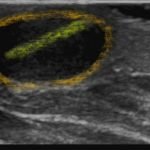

X-rays of the foot were obtained and no radiopaque foreign body was visualized. Due to high clinical suspicion for retained foreign body, a point-of-care ultrasound was performed by applying a high-frequency linear probe at the area of discomfort. In the long axis an ovoid focus of hypoechogenicity (orange outline) is visualized. Within this finding there is a linear focus (yellow line) of increased echogenicity measuring 1 mm in diameter and 1 cm in length. On short axis view, a rectangle focus (green dot) demonstrating shadowing (blue highlight) is seen.